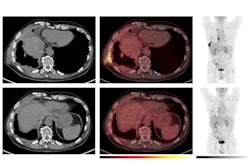

According to combined visual and semiquantitative analyses, of the 403 patients, 120 (30%) had normal brain F-18 FDG PET scans; two (< 1%) were abnormal but incompatible with a neurodegenerative disease, and 281 (70%) were classified as neurodegenerative.